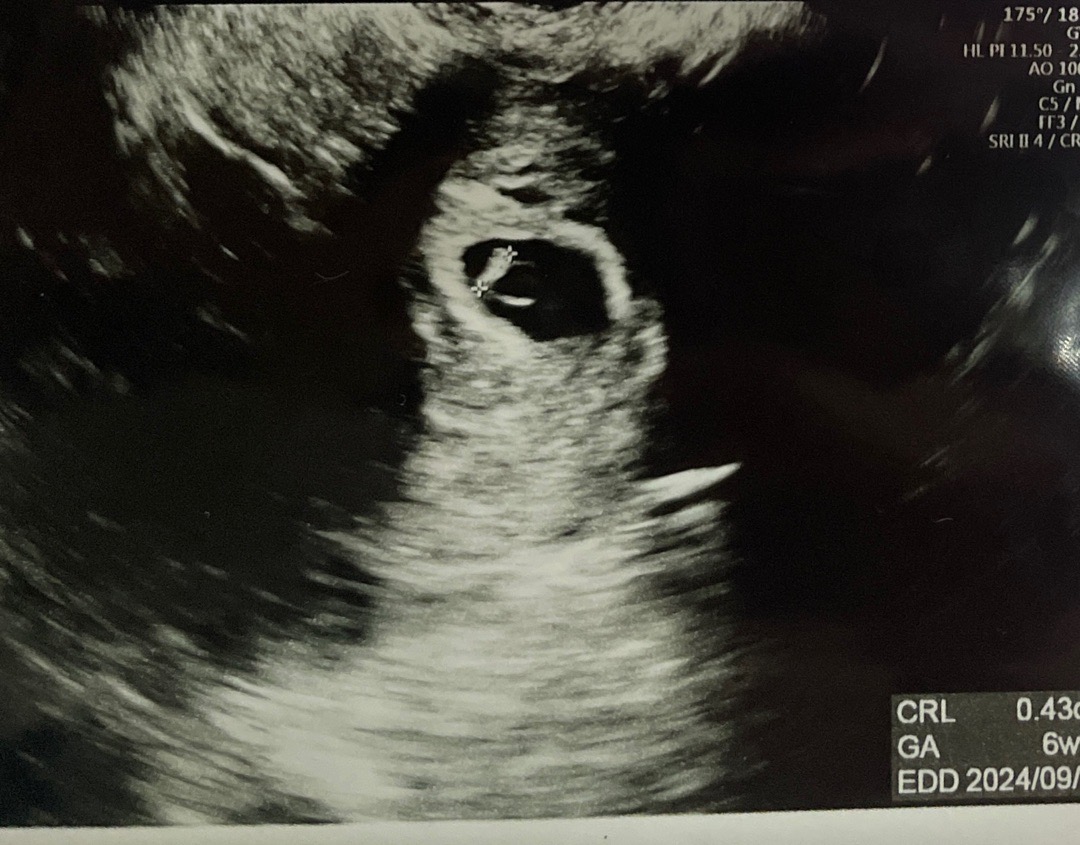

6주1일 병원가서 심소 듣고 왔어요❣️

빌리 기준 6주 1일인데 병원 가서도 6주로 듣고 왔어요^^ 4mm인데 자궁근종때문에 심장소리에 잡소음이 조금 있었지만 우리 아기가 무럭무럭 자라나고 있더라구요! 심장 뛰는 것도 보였어요 ❣️ 예정일 9월 6일 동일하게 받았네요 기분 좋아서 신랑이랑 외식하러 왔어요 ㅋㅋ 아참, 병원을 세번 바꾸면서 느낀거는 차라리 마음 편한 곳은 미혼 때 갔던 의원인 같아요. 병원은 너무 영업의 향기가 나고. 그래도 좋은거는 체계적이고 산모수첩이 무엇보다 퀄리티 있네요 ㅎㅎ 영양제 상담 받으면서 제가 평소에 너무 잘 챙겨먹어서 죄송했을 정도네요^^;; 앉으라고 해서 앉았는데 ㅠㅠ 아무튼 임산부 등록하구~ 아기 잘 큰것도 보구~ 이제 정말 임신한게 실감이 나요! 9월 베동분들 모두 파이팅입니다❣️❣️